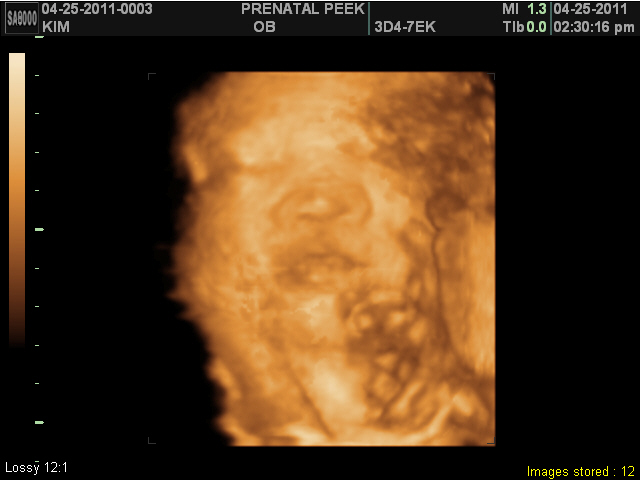

Prenatal Peak Round 2